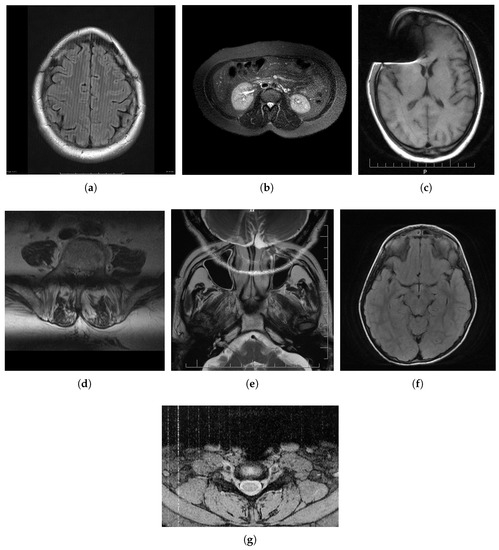

2. MRI Distortions